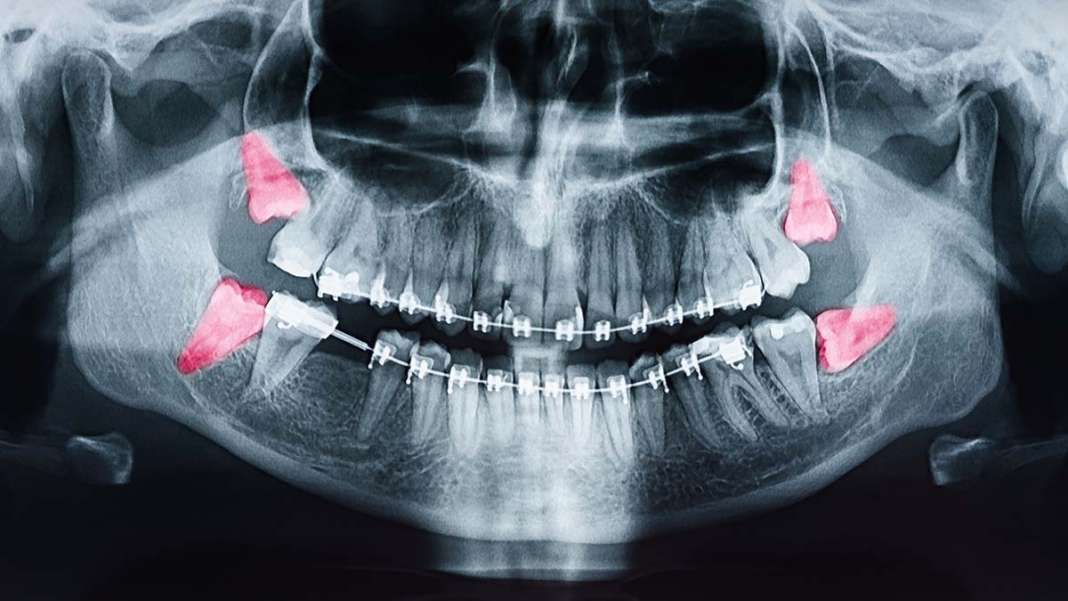

Časovni razmik med rastjo drugih zob in izraščanjem modrostnih zob je nadpovprečno dolg, poleg tega pa je izraščanje »osmic« pogosto nadpovprečno boleče. V ustih jih nemalokrat pričaka precej omejen prostor, zato modrostni zobje pogosto izrastejo pod zelo nenavadnimi koti, s čimer lahko ogrozijo sosednje zobe. Tako je velikokrat potrebno puljenje zob.

Šimpanzi so primati, ki se v tem pogledu najbolj približajo ljudem. Njihovo zobovje se namreč običajno dopolni okoli 12. leta starosti. Raziskovalca, ki sta se podpisala pod uvodoma omenjeno študijo, menita, da sta našla razlago za nenavadno počasno rast človeških zob. Izsledki njune raziskave dokazujejo, da je fenomen povezan z biomehaničnimi omejitvami med t. i. kraniofacialnim razvojem, torej razvojem lobanje in obraza. Zamik pri razvoju modrostnih zob je tako povezan z relativno počasnim kraniofacialnim razvojem pri človeku. Modrostni zobje začnejo izraščati šele takrat, ko je zanje vsaj teoretično na voljo dovolj prostora. Kot omenjeno, pa razpoložljivi prostor pogosto ni optimalen, zato lahko izraščanje zadnjih kočnikov privede do t. i. tesnega stanja zob.

Zakasnjeno izraščanje modrostnih zob pri ljudeh je neposredno povezano s počasnim razvojem čeljusti. Poleg tega pa je človeški obraz nadpovprečno kratek. Modrostni zobje tako čakajo na čim bolj optimalen trenutek, čas čakanja pa je lahko pri nekaterih ljudeh še posebej dolg. Izraščanje modrostnih zob je tako pogojeno tudi s povsem individualnimi dejavniki. Odvisno je predvsem od velikosti oziroma od hitrosti razvoja naše čeljusti in do razvitosti naših žvečilnih mišic, ki premikajo spodnjo čeljust. Če bi začeli modrostni zobje izraščati prezgodaj, bi jih pričakal sistem, ki še ne bi bil pripravljen nanje. Poskus uporabe prezgodaj izraslih modrostnih zob pri žvečenju bi najverjetneje privedel do poškodbe čeljustnega sklepa.